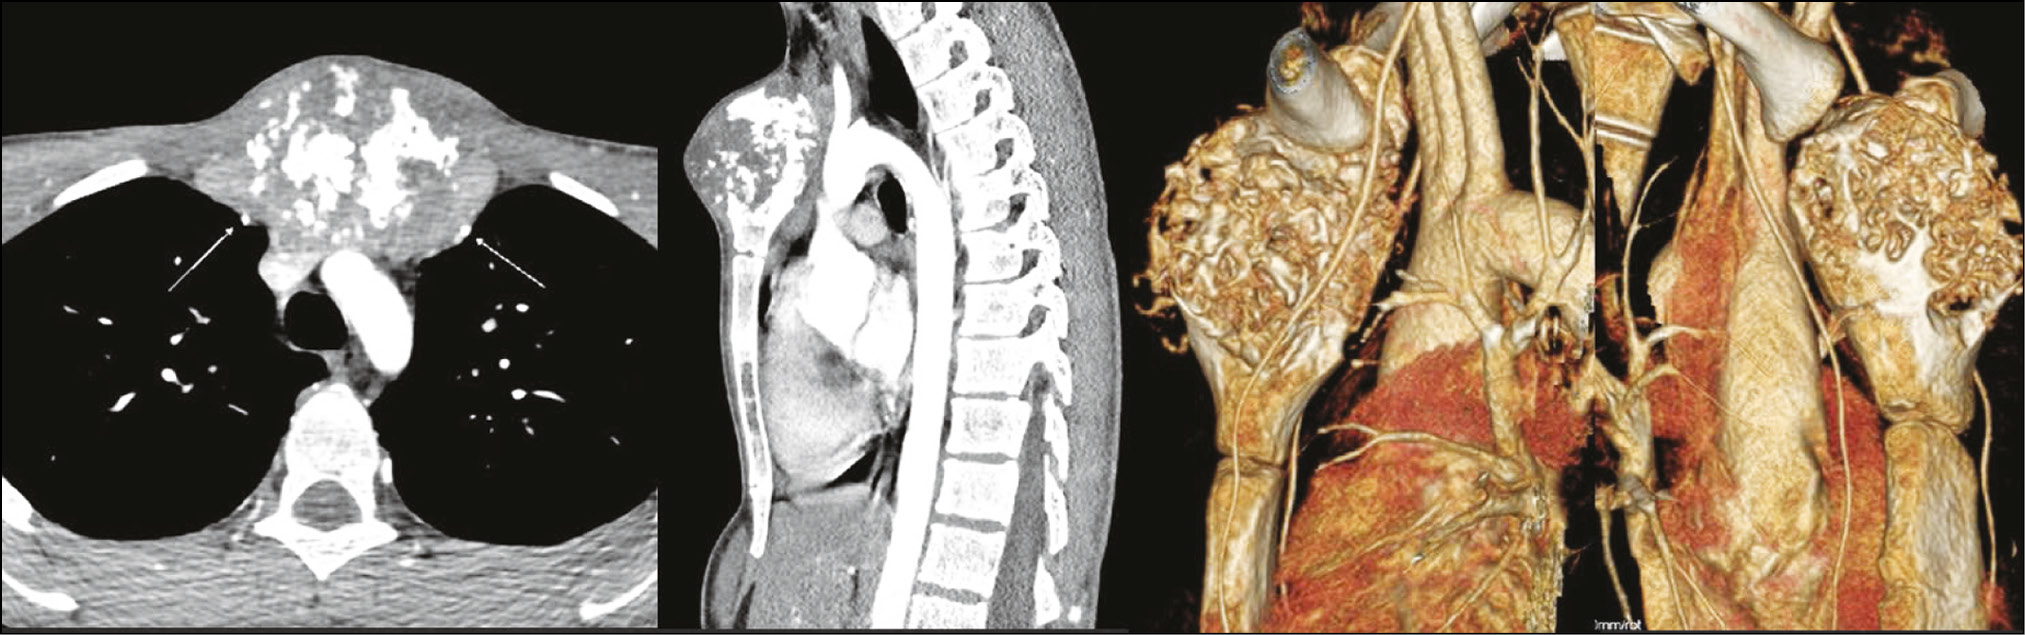

В качестве предоперационной подготовки дополнительно выполнена КТ с контрастированием (рис. 5). Отмечено интимное прилегание к внутренней грудной артерии слева и справа и аорте. Учитывая запланированный объём вмешательства и возможные интраоперационные риски, в операционной бригаде участвовали травматолог-ортопед, онколог, торакальный и сосудистый хирург.

Рис. 5. КТ-артериография с контрастированием аорты и внутренней грудной артерии пациента Г.

Пациент активизирован на 5-е сут в кольцах Дельбе для стабилизации плечевого пояса. На 14-е сут выписан на амбулаторное наблюдение по месту жительства. Корректор осанки грудного отдела позвоночника назначен на 3-й мес после оперативного вмешательства. Разработка движений в верхнем плечевом поясе под контролем реабилитолога — через 2 мес с момента операции. По контрольным снимкам через 12 мес признаков рецидива и нестабильности в импланте не обнаружено. Отмечена полная функция при движениях в плечевом поясе, признаков нестабильности имплантата по данным КТ не выявлено. Жалобы на боль и дискомфорт пациент не предъявляет (рис. 9).

Рис. 9. КТ-реконструкция положения протеза у пациента Г. и объём функции плечевого пояса через 1 год после операции.